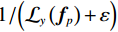

那么,当重建图像含有明显的噪声时,RTV最小化是否可以有效地区分重建图像中的结构和噪声?一个重要的先验知识是:在含噪图像中,图像有效结构处的偏导数往往具有相同的符号,而含有更多噪声区域内偏导数的符号往往是随机的。如图1所示:图1(a)是一幅含有明显噪声的重建图像;图1(b)是其中局部矩形区域的放大图;图1(c)是局部区域在着色后的偏导数图像。借此来说明含噪重建图像像素偏导数的特点,其中不同颜色代表不同大小的偏导数的值。可见,重建图像有效结构处偏导数的绝对值偏大并且大多数具有相同的符号,而含有更多噪声区域内偏导数的符号往往是随机的。

进一步从等式(10)和等式(12)可见,WTV首先是取偏导数的绝对值,然后再取偏导数的加权和。而WIV是首先取偏导数的加权和再取绝对值。对于WIV来说,由于图像f在局部矩形区域

$\mathcal{W}\left( p \right)$ 内任一点的偏导数有正负两种情况,所以直接求和会产生数值上的抵消。这样,对于包含更多噪声的局部矩形区域内的WIV值来说,这个区域内像素点的偏导数的符号往往是随机的,所以其加权和自然要小于包含更多有效结构的局部矩形区域内的WIV值。通过这样的方式,WIV作为惩罚权重可以在稀疏投影重建中自适应地保护图像结构和抑制噪声并且准确的重建图像结构。通过前文对RTV的分析可知,RTV最小化能够被使用在CT重建中,并且可以在很大程度上保护图像结构并抑制噪声。所以为了在稀疏角度下更精确地进行图像重建,本文在TV算法的基础上进行了改进。把RTV作为正则项引入至CT重建模型中,提出RTV最小化图像重建模型,其定义如下: